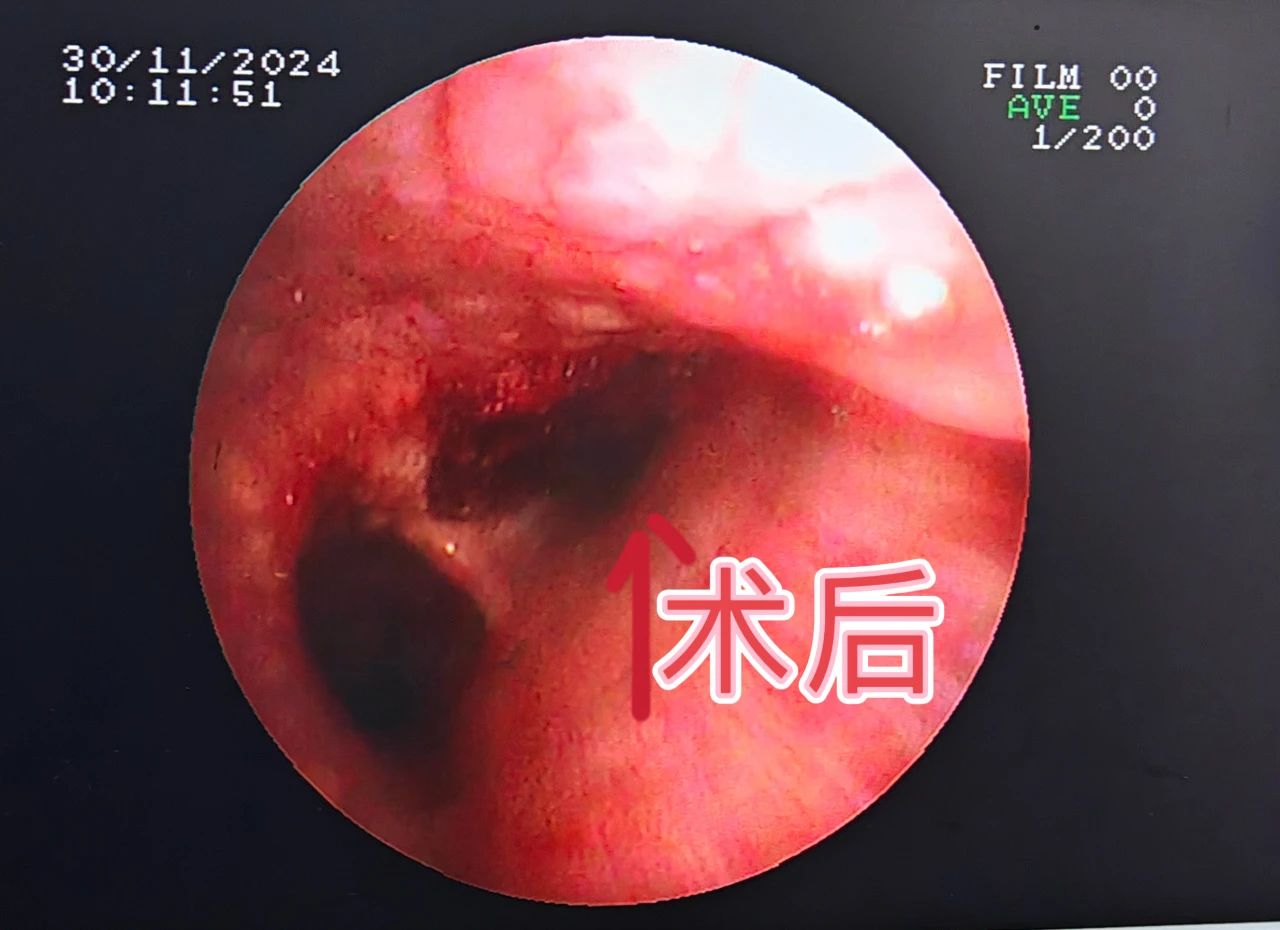

“支气管肿瘤”对人们来说比较陌生,它是呼吸系统的少见病症,以往的常规治疗手段是手术切除肿瘤后进行气管重建,手术难度大、风险高。为了减轻支气管肿瘤患者的身体负担,景德镇市第一人民医院呼吸与危重症医学科积极推动技术创新,成功引进并成熟开展多例经支气管镜高频电圈套切除术,为多名支气管肿瘤患者顺利“拆弹”,使患者们恢复畅快呼吸。 CT显示右侧气管内有巨大肿瘤 李大爷今年71岁,六个月前确诊为肺肉瘤样癌,一个月前间断性咳血,呼吸困难,最近感觉情况加重,到景德镇市第一人民医院呼吸与危重症医学科就诊。11月30日,患者出现意识模糊、血气提示急性呼吸衰竭。 “呼吸的通道堵塞严重,情况很危险,随时都可能窒息。”市一院呼吸与危重症医学科主任卢志军介绍。通过综合评估患者年龄、耐受能力、影像学特征,呼吸与危重症医学科团队最终决定对患者实施支气管镜高频电圈套器肿瘤切除术。“这样可以切除病灶,迅速解除气道阻塞,缓解症状”。 卢志军正在进行支气管镜手术(资料图片) 术前工作准备就绪,手术紧张有序的进行。随着气管镜进入患者的主气管时,看到患者右侧主气管内一个圆形“硕大”的肿瘤,卢志军通过电圈套器对肿瘤进行套扎,同时使用氩气刀辅助切割和止血,肿瘤顺利切除,随后采取冷冻处理减少肉芽和肿瘤组织生长,最后使用电凝术对肿瘤根部进行最后的处理和止血,手术用时仅15分钟,最终气道顺利再通,末梢血氧也由术前的60%升至正常。李大爷现已顺利出院。 术前术后对比图 经支气管镜高频电圈套切除术是呼吸内镜下支气管肿物切除术常用手段之一,通过纤支镜检查可以在镜下直视气管、支气管的粘膜是否发生病变、管腔是否通畅,通过对病变部位进行组织活检、刷检以及肺泡灌洗可协助疾病诊断。此外,通过支气管镜还可以进行较多的镜下治疗,高频电圈套就是其中一种。该项技术利用高频电圈套将气管内的新生物套住,自新生物根部将其切除,高频电圈套的优点是可以切除较大块的肿物,并且出血少、安全性高、患者花费低、操作时间短,甚至仅使用局部麻醉就可以完成,与全身麻醉相比,并发症少,安全性更高。对于气管、支气管的气管息肉、良性肿瘤、平滑肌瘤及恶性肿瘤的姑息治疗,有较好的治疗效果。 呼吸与危重症医学科简介 景德镇市第一人民医院呼吸与危重症医学科成立于2010年10月,经过不断发展壮大,现已形成具有规模和专科医疗特色的医教研全面发展的科室,2020年与江西省胸科医院为省市共建学科。 科室开放普通床位 98 张,重症监护床位 6 张。配有医师 19人,护士 64人,其中医师高级职称 6人,主治医师 9人,住院医师 4 人,副主任护士4人,主管护师 4人等,其中硕士 5 人。 除了呼吸科常见病、慢性阻塞性肺病、各种呼吸衰竭及间质性肺病、肺结节病及肺心病等呼吸危重症疾病的诊治,近年来,科室不断开展了肺癌的早期诊断及个性化治疗,支气管镜检查、内科胸腔镜检查及各种介入治疗,及置入细管胸腔闭式引流术治疗气胸及胸腔积液, 经彩超或 CT 引导经皮肺穿刺活检技术,经支气管镜肺活检,肺段灌洗,钳取异物,经支气管镜引导气管插管术,经支气管镜氩气刀治疗技术、冷冻治疗技术,球囊扩张,支架植入治疗恶性肿瘤大气道狭窄,内科胸腔镜诊疗技术,经皮穿刺置入 125I 粒子治疗肺恶性肿瘤技术,床旁支气管镜检查等各种急危重症救治技术等。还有已购入超声支气管镜和硬质支气管镜,即将开展超声支气管镜检查及淋巴结穿刺活检术,硬质支气管镜技术等。